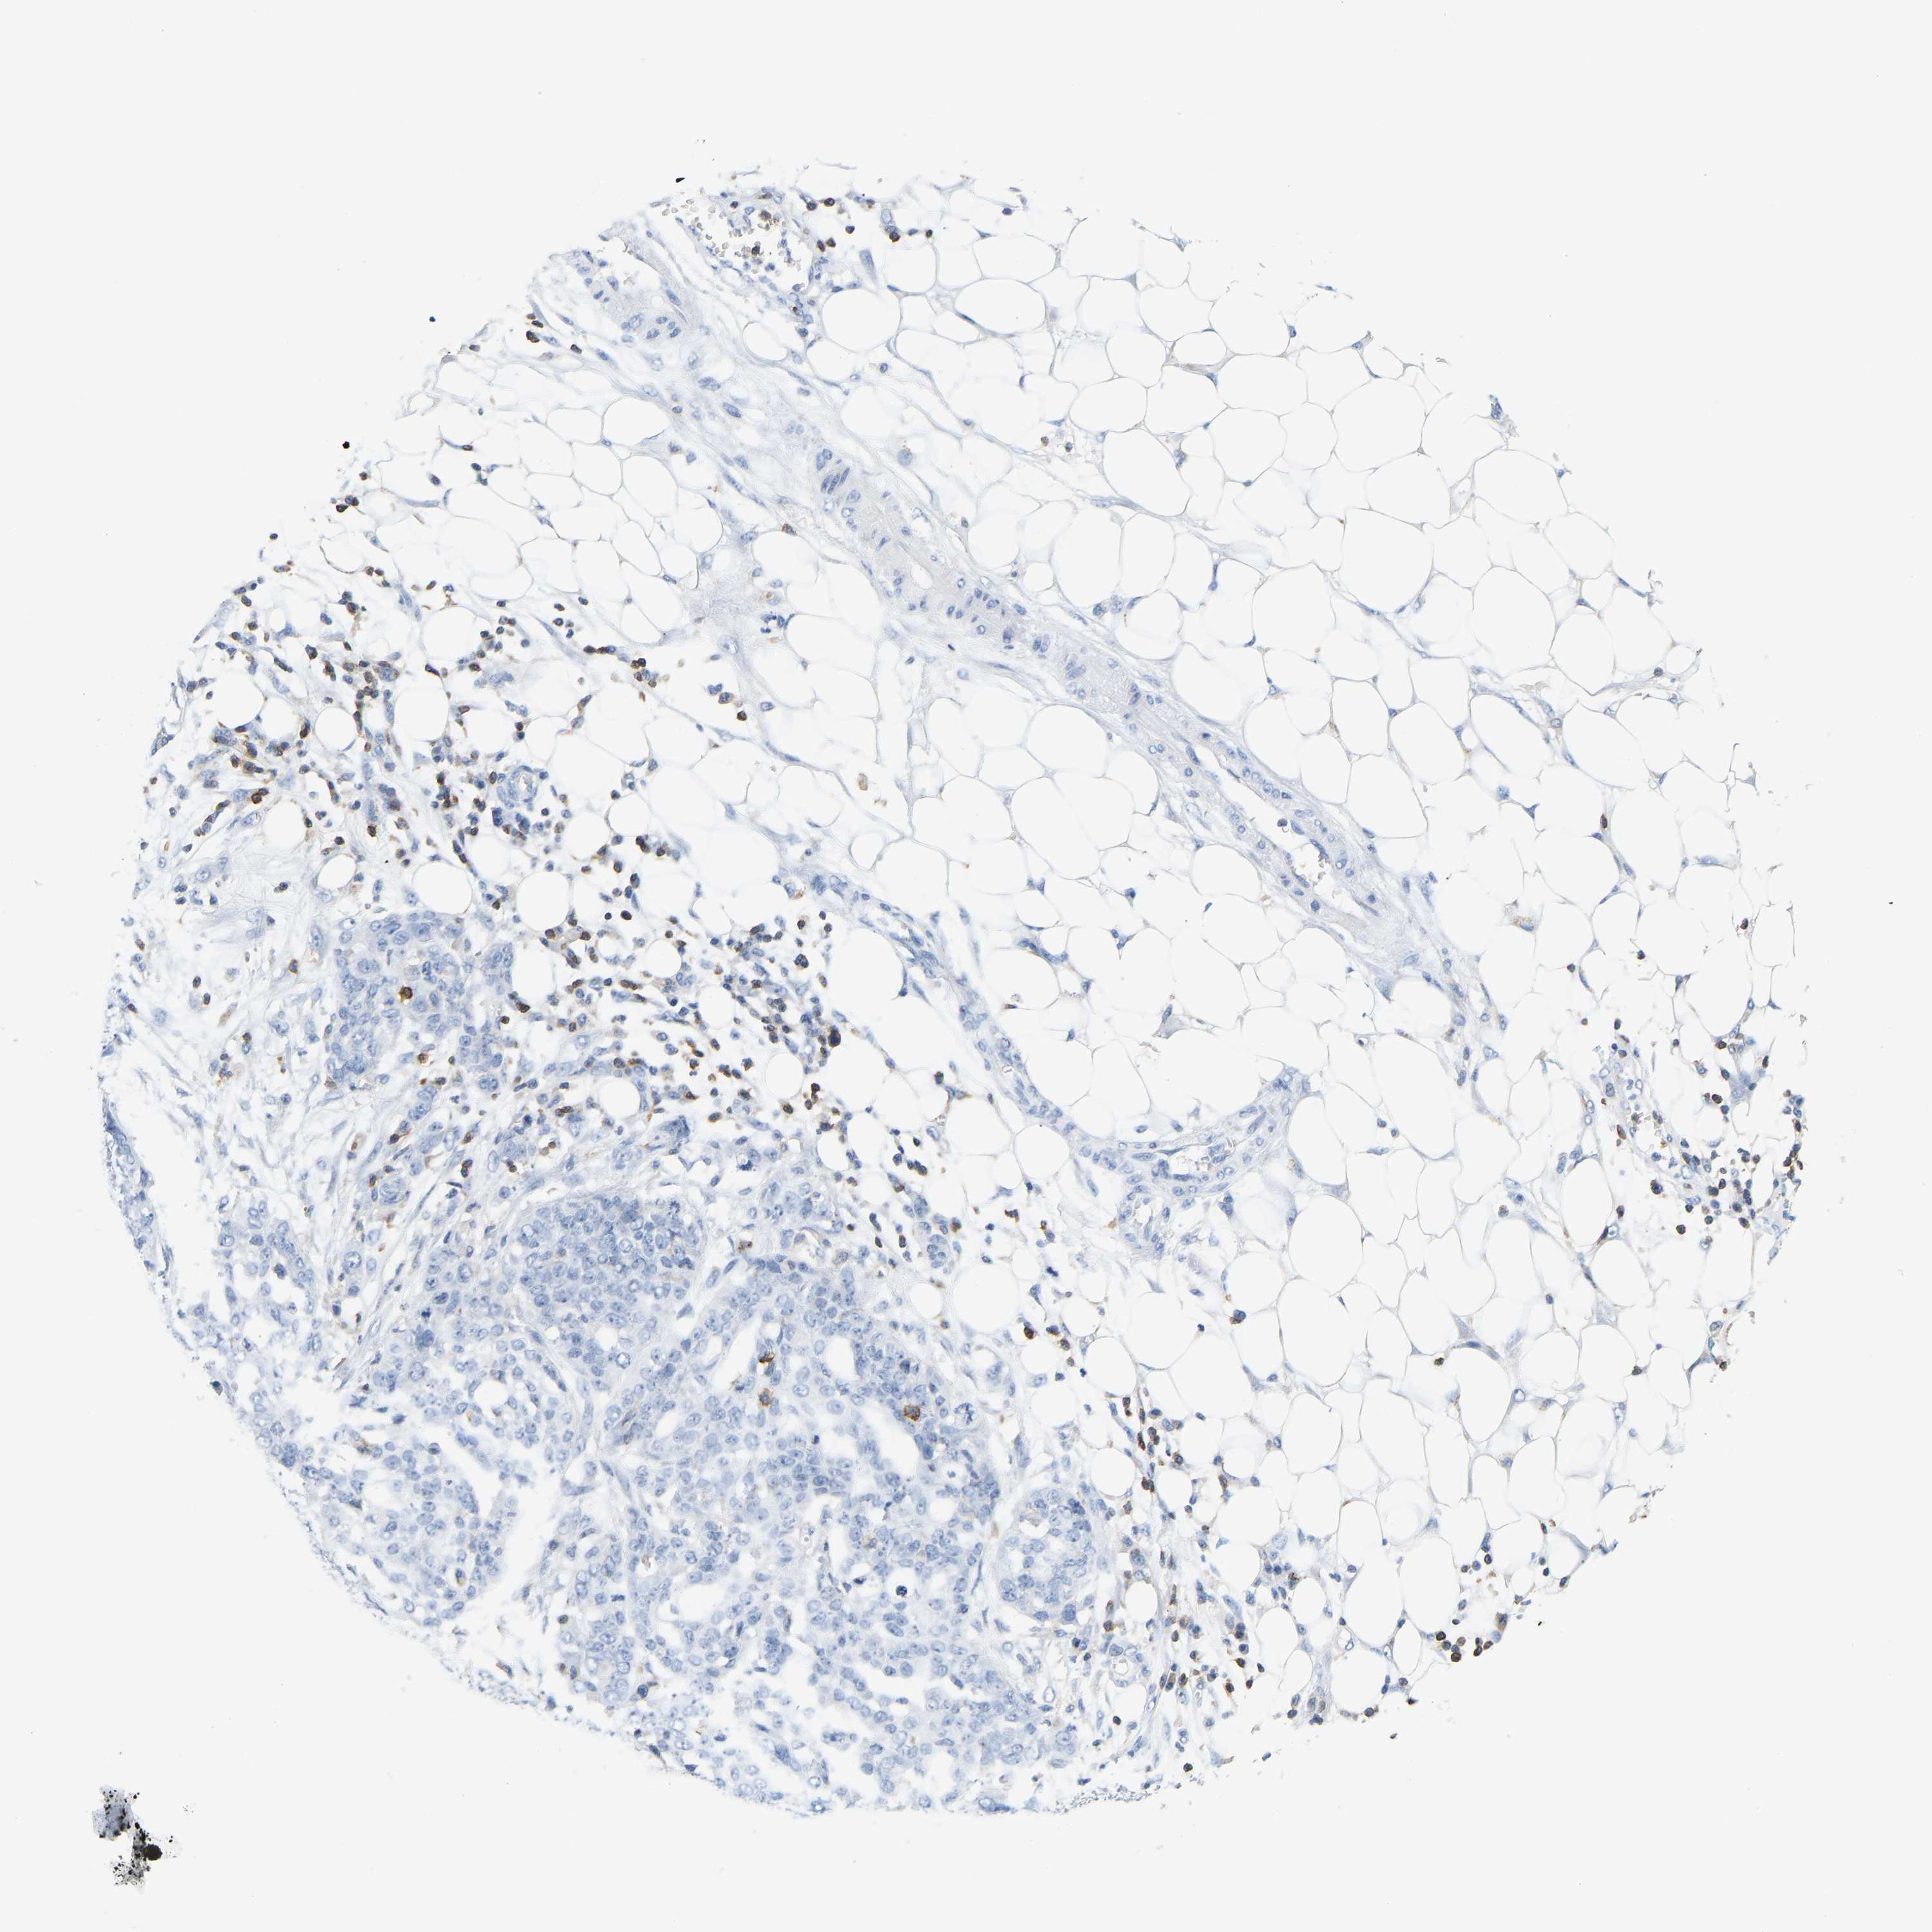

OVARIAN CANCER - Protein expressioni

A mouse-over function shows sample information and annotation data. Click on an image to view it in a full screen mode. Samples can be filtered based on level of antibody staining by selecting one or several of the following categories: high, medium, low and not detected. The assay and annotation is described here.

Note that samples used for immunohistochemistry by the Human Protein Atlas do not correspond to samples in the TCGA dataset.

Antibody stainingi

Antibody staining in the annotated cell types in the current human tissue is reported as not detected, low, medium, or high, based on conventional immunohistochemistry profiling in selected tissues. This score is based on the combination of the staining intensity and fraction of stained cells.

Each image is clickable and will lead to virtual microscopy that enables deeper exploration of all samples and also displays staining intensity scores, fraction scores and subcellular localization as well as patient and tissue information for each sample.

Antibody CAB033987

Cystadenocarcinoma, mucinous, NOS